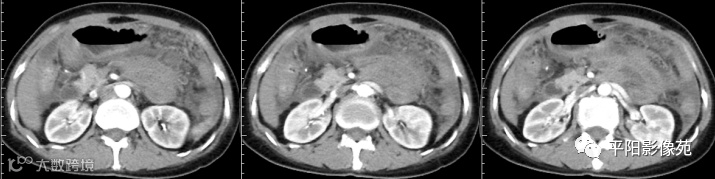

腹部增强 延迟期

壁腹膜增厚伴或不伴腹水;增厚的腹膜光滑、均匀,呈线带状,部分可见腹膜结节,网膜及肠系膜广泛浸润性改变;增强扫描明显强化。

合并淋巴结肿大,可钙化,若中心干酪样坏死,增强扫描环形强化

湿型:渗出性高密度腹水(CT值20-45HU),高密度由于高蛋白和细胞含量多可能。

干型:干酪性肠系膜淋巴结病、纤维粘连、增厚,网膜饼状改变